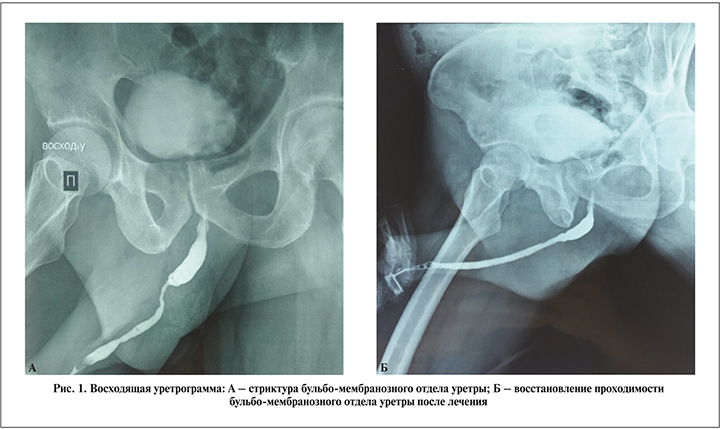

Результаты и обсуждение. Локализация стриктур уретры при САЛ превалировала в бульбозном отделе у 36 (65,5%) больных, у 16 (29,1%) – в пенильном отделе и ладьевидной ямке, у 3 (5,5%) – в простатическом отделе (рис. 1).